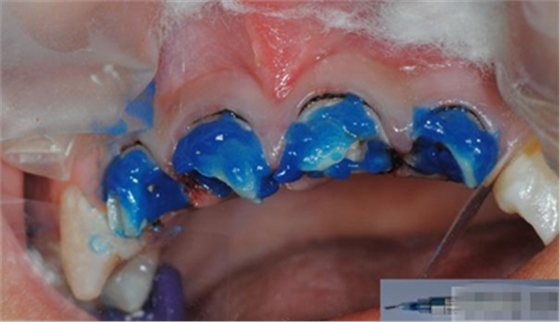

沖洗注意點(diǎn):

1.酸蝕后沖洗時(shí)間要充分,最少20s---1min(沖洗時(shí)間>酸蝕時(shí)間)2.沖洗不要用自來水,相當(dāng)于二次污染 3.不含油霧壓縮空氣吹干牙面

組織過于干燥會(huì)影響粘結(jié)效果。而且通常也會(huì)導(dǎo)致術(shù)后敏感。酸蝕后牙本質(zhì)不應(yīng)吹干。沖洗掉酸蝕劑后洞型用氣槍吹干,但要組織保持濕潤非常重要。牙本質(zhì)看起來應(yīng)該是反光的,而不是白堊狀。

將粘結(jié)劑在牙體硬組織上充分涂布20秒,最少2次,然后,輕輕吹干,固化。理想的粘接劑的厚度不應(yīng)超過50微米。如果粘接層過后可能會(huì)發(fā)生微滲漏,過薄則可能彈性不足。飽和粘接系統(tǒng)第一層厚度可以達(dá)到30-40微米,有時(shí)也會(huì)超過此值。但這個(gè)厚度對(duì)于一些情況不適用,如嵌體粘結(jié)。80-100微米厚度的粘接層難以形成持久的固位力。電子顯微鏡照片顯示飽和粘接系統(tǒng)會(huì)形成較厚的粘接層,并且,其內(nèi)部充滿氣泡,optibond和PQI就屬于飽和粘結(jié)系統(tǒng)。Dr.Vanini的建議最好使用不飽和粘結(jié)系統(tǒng),因?yàn)椋柡驼辰Y(jié)系統(tǒng)往往會(huì)形成過厚的粘結(jié)層。Dr.Vanini使用ENA bond粘接系統(tǒng),在單層應(yīng)用時(shí)厚度為8微米,2層為12微米,3層為25微米。三層粘結(jié)劑所形成的粘接力值可以達(dá)到49MPa(N/平方MM)。使用非飽和粘結(jié)系統(tǒng)進(jìn)行2-3層的粘接方法的另一個(gè)優(yōu)點(diǎn)是可以減少術(shù)后過敏癥狀的出現(xiàn)。